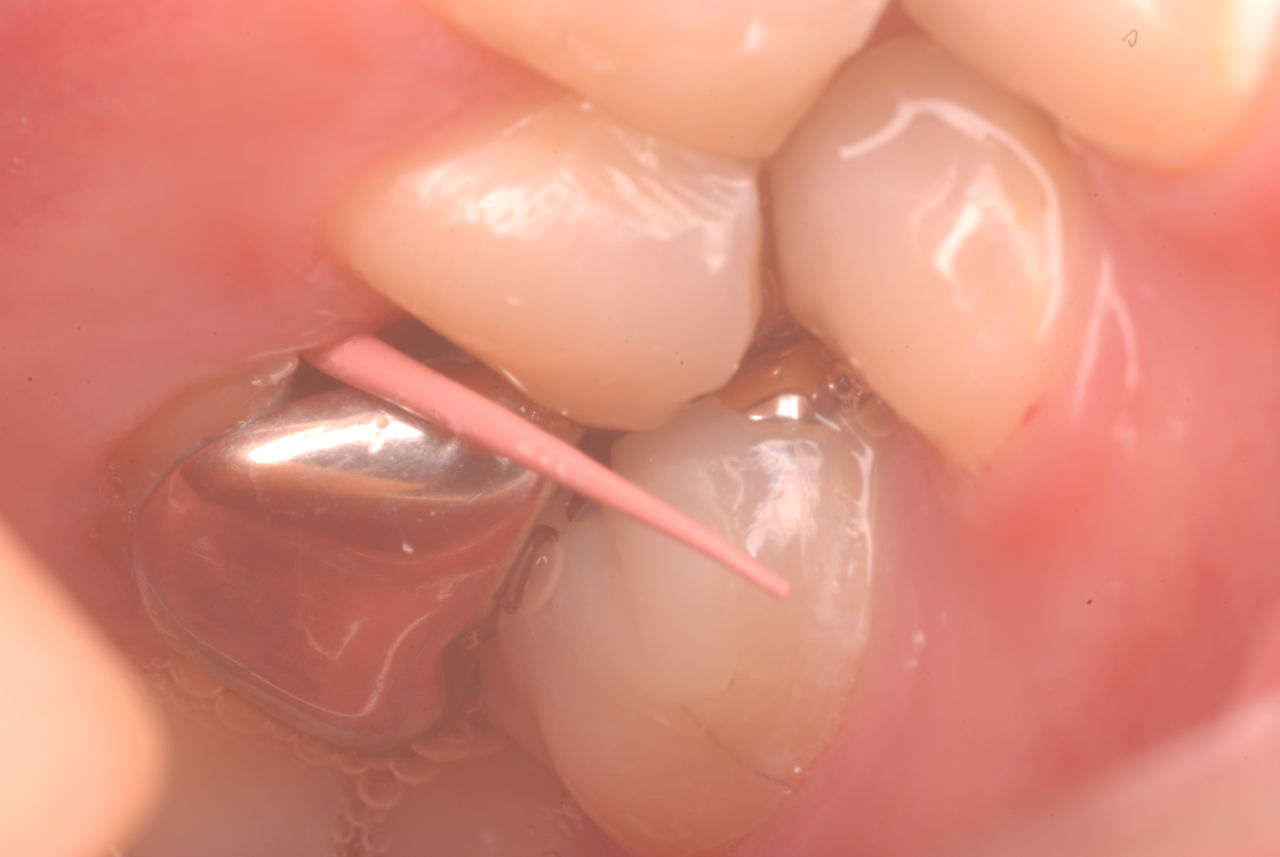

入れ歯の話から入りました。色々不満で注文があるようです。でも話が一段落して口腔内を調べると殆どの歯が重症で抜けそうな歯だらけなのです。

ご自分でやられても歯茎から血が出ないと話をされていましたが、私がブラシを当てると悲惨な状態であることがわかりました。

何故歯が悪くなるのか、歯周病で抜けるのか分からなければ何を入れても歯は悪くなり抜けていくのです。

病気を治しましょう。それから差し歯や入れ歯を入れましょう!物を入れれば入れるほど、磨き方や掃除の仕方が上手にならなければ、すぐ抜けてくるのです。